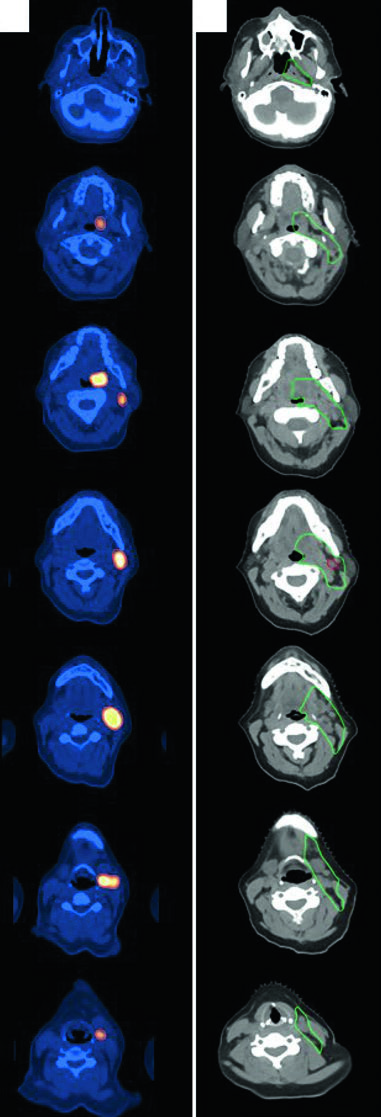

DLBCL de Cabeça e Pescoço

Uma mulher de 47 anos com DLBCL estádio IIA de tonsila esquerda e pescoço esquerdo (nível 2, 5,6 cm) recebeu 3 ciclos de R-CHOP seguidos de RT consolidativa. Simulada com pescoço em extensão, imobilizada com máscara aquaplast de 5 pontos. O CTV ISRT cobre toda a tonsila esquerda e o nível ganglionar envolvido, incluindo 1–2 cm superior e inferior à extensão pré-quimioterapia. Casos de linfoma de cabeça e pescoço exigem atenção especial ao registro entre PET diagnóstico e CT de simulação.